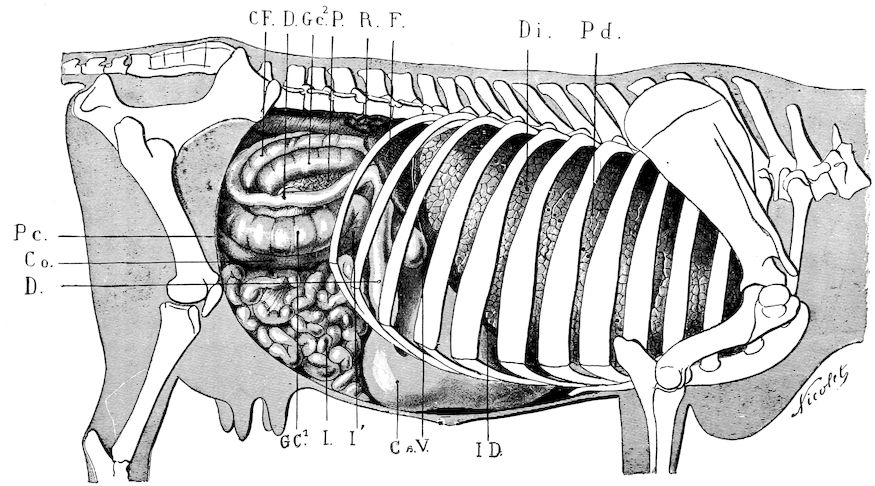

Fig. 1.—Rachitis in a young goat.

Rachitis is a disease of youth, and is common both to the human species and to all domestic animals. It is characterised by irregularities in development and by imperfect consolidation of the bones. The boundary between rachitis and osseous cachexia is difficult to define and in fact at the present moment the two diseases can scarcely be defined with exactitude. Rachitis again is often complicated with softening of the bones, disease of the limbs, arrested development, etc., but it must not be forgotten that although the irregularities in ossification and development of the skeleton are the symptoms most striking to the eye, they do not stand alone, and that from the point of view of development all the tissues, including the muscles, are more or less affected and that most of the physiological functions such as digestion and the secretion of urine are deranged.

Symptoms. The onset is absolutely insidious and the diagnosis of rachitis is never made until nutrition has long been abnormal.

This disturbance of nutrition is revealed by irregularity and abnormality in appetite, by difficulty in rising and moving about, and by the animals lying down for long periods. The subjects are feeble, sluggish and badly developed.

Next supervenes the second phase characterised by deformity of bones. This is of two kinds—deformity in the neighbourhood of joints (deformity or enlargement of the epiphyses) and deformity of the diaphyses. The former results from irregularity in ossification of the articular cartilages. The latter is followed by loss of rigidity in the bones of the limbs which, under the influence of the body weight and of muscular contraction, bend in different directions.

The bones appear of increased thickness principally towards the 6articulations. The latter are deformed, and on palpation are found to be surrounded by uneven and irregular growths.

The front limbs are distorted. In young pigs, lambs, and less frequently in foals, calves and dogs, the jaws become deformed, and mastication is rendered difficult.

The vertebral column may also be affected, and lordosis (bending downwards of the back) or skoliosis (lateral bending of the back) is somewhat frequent.

Cyphosis, or upward bending of the back, seldom occurs, and when seen, sometimes results from disease other than rachitis.

General development is always interfered with and the young creatures are generally dwarfed.

The digestive apparatus is disordered, the appetite is irregular and sometimes depraved, while indigestion, gastritis, and enteritis are not exceptional. Physiological and pathological research has shown that the quantity of phosphoric acid eliminated in twenty-four hours in a rachitic child is double the quantity passed by a healthy infant. The amount of urea in the urine (which is a criterion of nutrition, and usually varies in proportion to the amount of food ingested) is, on the contrary, diminished even when highly nitrogenous food is given, thus suggesting diminution in nutrition.

Lesions. The lesions are represented by abnormal and irregular thickening around the interarticular cartilages. The cartilage is thickened, compressible, very spongy and without regular ossification. Diffused periostitis exists principally towards the extremities of the bone. Beneath the periosteum the surface of the bone appears rough and softened. On section the medullary canals are seen to be enlarged and filled with marrow of a gelatinous character. The Haversian canals are dilated, and the entire tissue appears very vascular. Chemical analysis proves that the mineral constituents of the bone, particularly the phosphates, have diminished by one-half; the organic constituents on the other hand are increased in a similar ratio, but the ossein is abnormal. Ossification has, in a word, been incomplete.

7Diagnosis. Diagnosis presents no difficulty except in the early stages before deformity has occurred.

Rachitis can scarcely be mistaken for any other condition except perhaps infectious rheumatism, but the rapid course of the disease in the latter case, the persistence of fever and the swelling of the joint cavities sufficiently differentiate the conditions provided care is exercised.

Prognosis. From an economic point of view the prognosis is very grave for if the lesions are extensive there is nothing to be gained by keeping the animal.

Treatment. Treatment differs very little, whether the animals are still being suckled or have been weaned. In the former case it is necessary to improve the quality and chemical constitution of the mother’s milk by giving food, richer both in mineral salts and in nitrogenous material.

Cooked grains, milk, and forage of good quality should be given freely. When the mothers are exhausted and anæmic it is better to feed the little animals artificially or to change them to a foster-mother. Those already weaned should be given good rich milk, eggs, boiled gruel, and drugs, such as the phospho-chlorate of lime, 1 to 1½ drachms per day (for a calf); lacto-phosphate of lime, 1 to 1½ drachms; bi-phosphate of lime, 1 drachm, or simply ordinary phosphate of lime. Oil containing 1 per cent. of dissolved phosphorus may be given in doses of 1 to 2½ drachms, according to the size of the calves, but its use calls for much care, and it should only be given for alternate periods of a fortnight. The glycerophosphates are not very active. Beef meal in doses of 6 drachms to 1½ ounces and chloride of ammonium in doses of 30 to 60 grains have also been used advantageously. The above drugs, but particularly the bi-phosphate of lime and chloride of ammonium, stimulate nutrition and diminish the quantity of phosphoric acid eliminated.